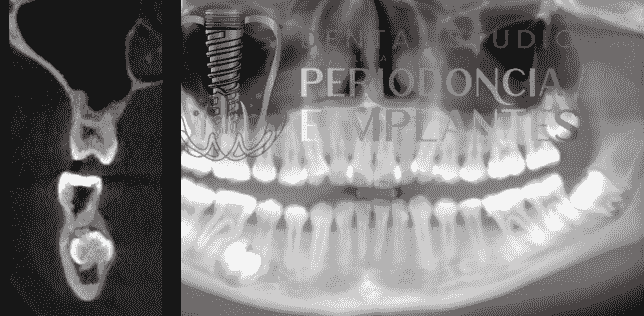

Tecnología Avanzada

Utilizamos equipamiento de última generación para asegurar un diagnóstico preciso y un tratamiento efectivo, facilitando así una experiencia cómoda y segura.

Implantes Dentales

Realizamos la colocación de implantes dentales con planificación computarizada, asegurando una integración óptima y duradera en tu boca, así como un seguimiento continuo para prevenir complicaciones.